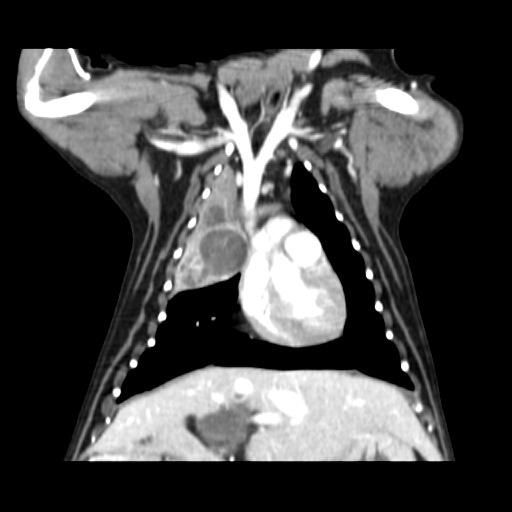

엑스레이 사진과 CT 사진(흉부 앞, 우측 옆)은 첨부하였습니다.

폐 우측 위쪽에 원발성 암이 발생한 것으로 보였습니다.

식도와 심장을 눌러서 기침을 발생시켰습니다.

나쁜 소식은 심장과 혈관이 위치한 안 좋은 부위에 암이 있다는 것이고,

좋은 소식은 심장과 혈관과 아직 붙지 않고 떨어져 있다는 것이었습니다.